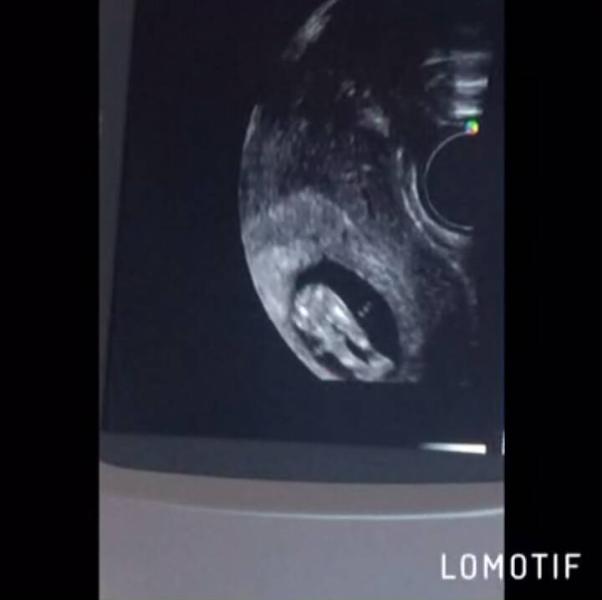

сходили мы с маськой на узи-контроль. все у нас хорошо, развивается тоже соответственно сроку. такой активный ьыл и сердитый 😂 сказали более70% что мальчик, пипиську показал, но могут и ошибиться на таком сроке конечно. но у нас небольшой тонус по передней стенки и низкое расположение планцеты. сказала узиска покой физический, интимный, тяжести не поднимать. у кого так же было на моем сроке?? что назначали?? к врачу 4 июля и на генетику сдать. переживаю очень (((

@lerochka1995 у меня видео целое 😂 подруга снимала на телефон все узи. но этот момент я обожаю когда ножки вытянул 😊